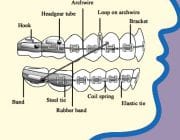

[/fusion_tab][fusion_tab title=”Aparate fixe: Aparatul ortodontic metalic” icon=””]Aparatul ortodontic metalic este cel mai des intalnit tip de aparat dentar, iar noile tehnologii au facut ca purtarea aparatului sa fie mult mai confortabila azi decat a fost anii trecuti. Componenetele aparatului dentar sunt facute din otel de inalta calitate. Aveti optiunea de a adauga elasice colorate pentru un design mai vesel si mai unic, cerinta intalnita mai ales la copii. Deoarece este foarte simplu sa schimbi aceste culori aparatul se poate personaliza la fiecare vizita la ortodont.

[/fusion_tab][fusion_tab title=”Aparate fixe: Aparatul ortodontic metalic” icon=””]Aparatul ortodontic metalic este cel mai des intalnit tip de aparat dentar, iar noile tehnologii au facut ca purtarea aparatului sa fie mult mai confortabila azi decat a fost anii trecuti. Componenetele aparatului dentar sunt facute din otel de inalta calitate. Aveti optiunea de a adauga elasice colorate pentru un design mai vesel si mai unic, cerinta intalnita mai ales la copii. Deoarece este foarte simplu sa schimbi aceste culori aparatul se poate personaliza la fiecare vizita la ortodont.